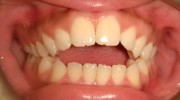

Pretreatment - Patient on Presentation